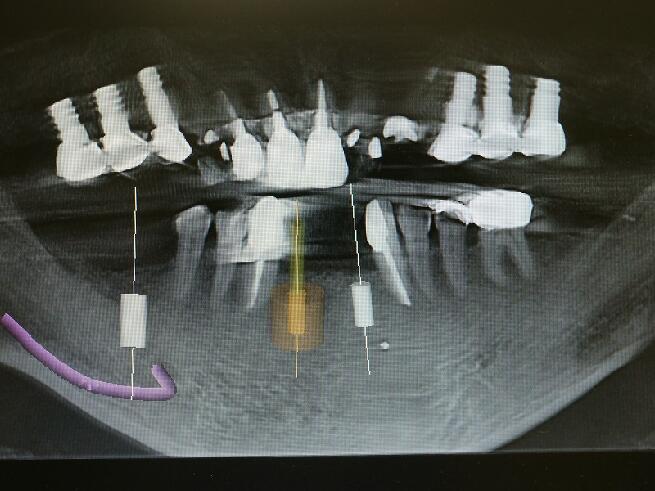

下顎の前歯の2番目の側切歯の位置へのインプラント埋入手術のCT写真上でシュミレーションして

いるところです。3ミリのインプラント体を埋入するには骨が薄すぎます。ドリルでの切削では外側の壁に穴が開いたりドリルが突き抜けたりします。大変危険ですが多くの大学病院や歯科医院ではドリリングで対応してるのが現状です。

前面から見た写真です(オレンジ色の部位です)